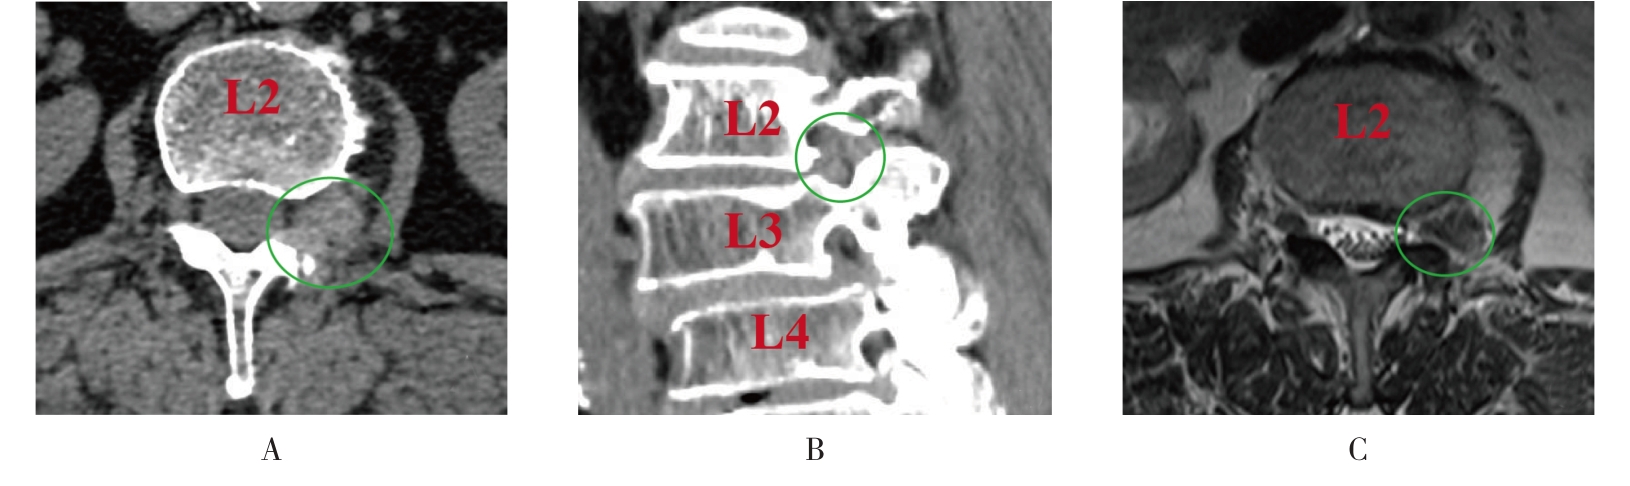

• 单通道非同轴脊柱内镜经椎间孔外入路(椎板外切迹)治疗极外侧椎间盘突出症的临床疗效观察

2026, 32(3):28-36. DOI: 10.12235/E20250050

摘要 (43) HTML (65) PDF 6.88 M (47) 评论 (0) 收藏

摘要:目的 观察单通道非同轴脊柱内镜经椎间孔外入路(椎板外切迹)治疗极外侧椎间盘突出症(FLLDH)的临床疗效。方法 回顾性分析2022年5月-2024年5月该院收治的,行单通道非同轴脊柱内镜经椎间孔外入路(椎板外切迹)治疗的FLLDH患者70例。于术前和术后,评估腰腿疼痛程度、腰椎功能和临床疗效。结果 相较于术前,术后3 d和3个月,患者下肢视觉模拟评分法(VAS)评分、腰部VAS评分、Oswestry功能障碍指数(ODI)、数字分级评分法(NRS)评分和Roland-Morris功能障碍问卷(RMDQ)评分明显降低,日本骨科协会(JOA)评分明显升高,差异均有统计学意义(P < 0.05);改良MacNab评分标准显示,末次随访时的优良率为94.28%。结论 单通道非同轴脊柱内镜经椎间孔外入路(椎板外切迹)治疗FLLDH,能明显改善患者腰腿疼痛和腰椎下肢功能,其具有创伤小、易操作、安全性高和疗效好等优点,值得在临床推广应用。